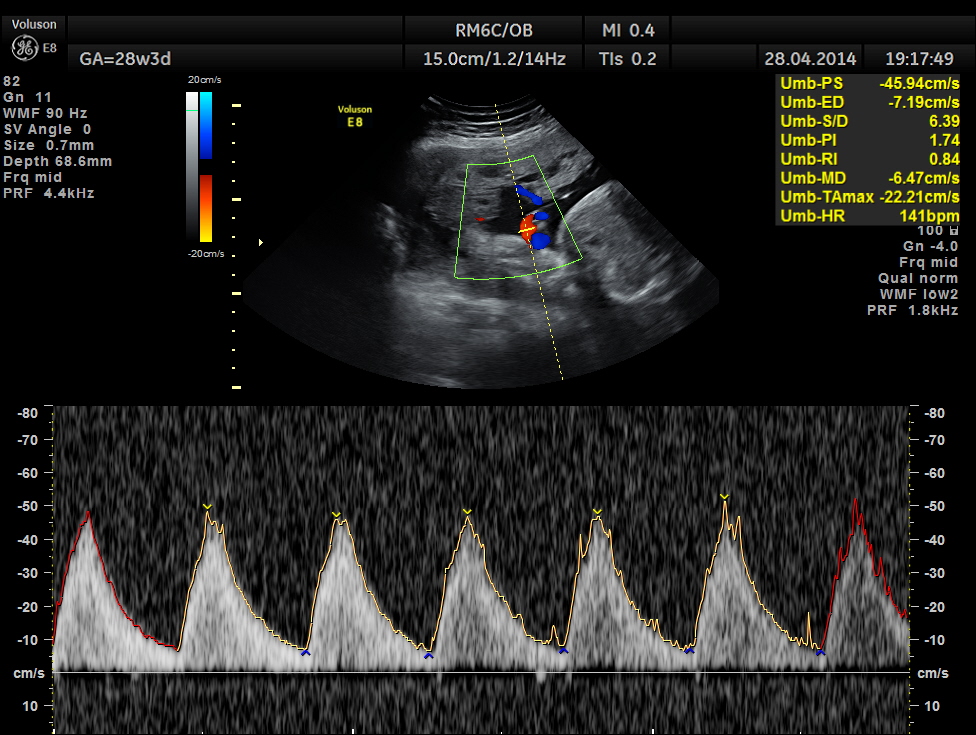

Spectral Doppler pictures are given below.

Umbilical arterial arterial P.I. and R.I. are high for the GA. and the cerebro placental ratio appears to be borderline > 1.0 and < 1.1 for the R.I.

Umbilical artery doppler appears to be normal for the GA.